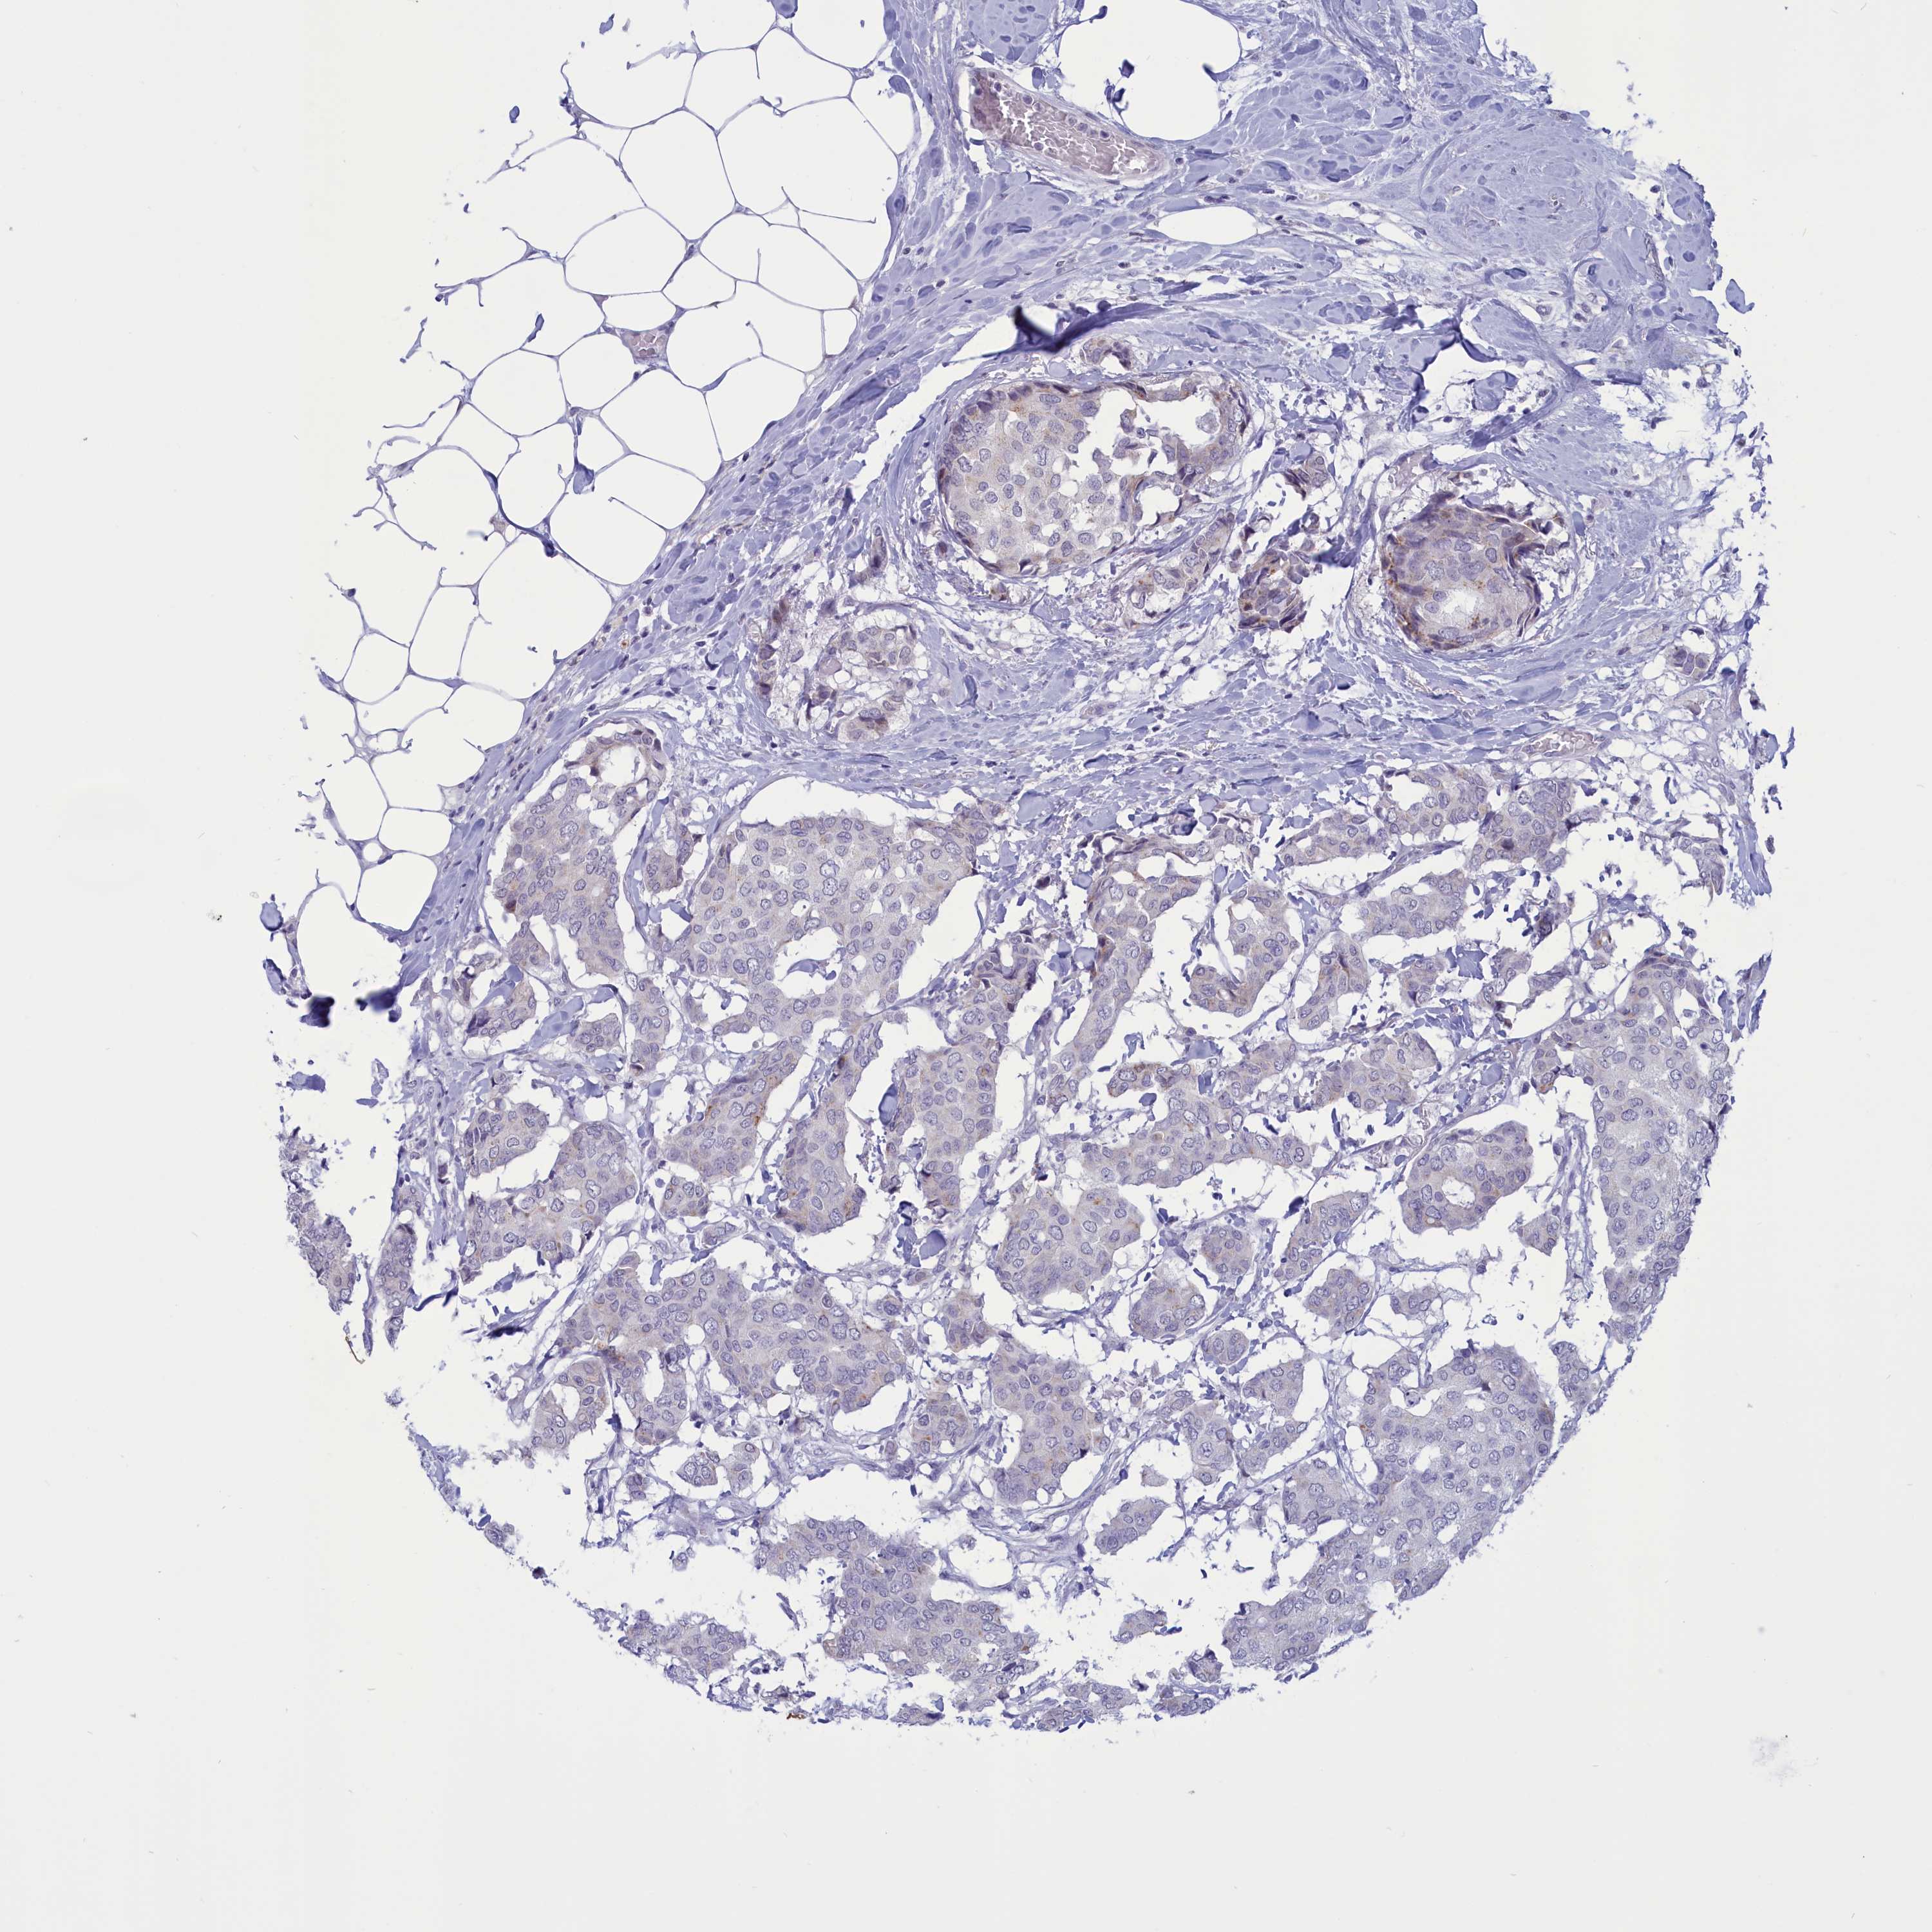

CANCER BREAST CANCER Show tissue menu

BRCA TCGA BRCA VALIDATION PROTEIN EXPRESSION